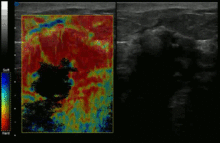

Elastography shows stiff cancer tissue on ultrasound imaging.

-

Ultrasound image shows irregular shaped mass of breast cancer.